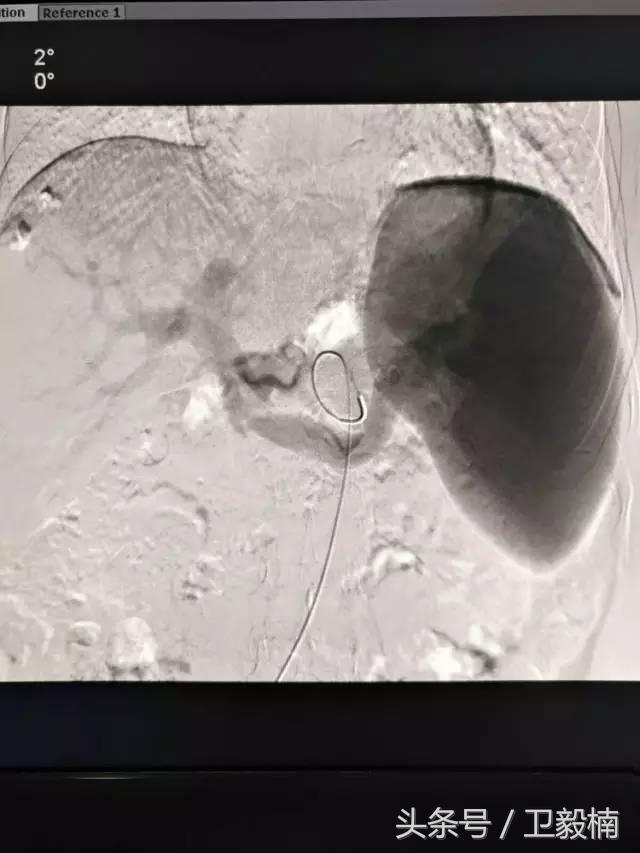

2、经导管血管栓塞法(Transcatheter embolization)

经原血管造影的导管或特制的导管,将栓塞物送至靶血管内,一是治疗内出血如外伤性脏器出血、溃疡病、肿瘤或原因未明的脏器出血。另一是用栓塞法治疗肿瘤,因肿瘤循环部分或全部被栓塞物阻断,以达控制肿瘤之生长,或作为手术切除的一种治疗手段;亦可用于非手术脏器切除,例如注射栓塞物质于脾动脉分支内,即部分性脾栓塞,以治疗脾功亢进,同时不影响脾脏的免疫功能。

常用的栓塞物质如自体血凝块、明胶海绵、无水酒精、聚乙烯醇、液体硅酮、不锈钢圈、金属或塑料小球及中药白芨等。

(3)应用栓塞材料,钢圈,内支架治疗动脉瘤、AVM、动静脉瘘,血管性出血。